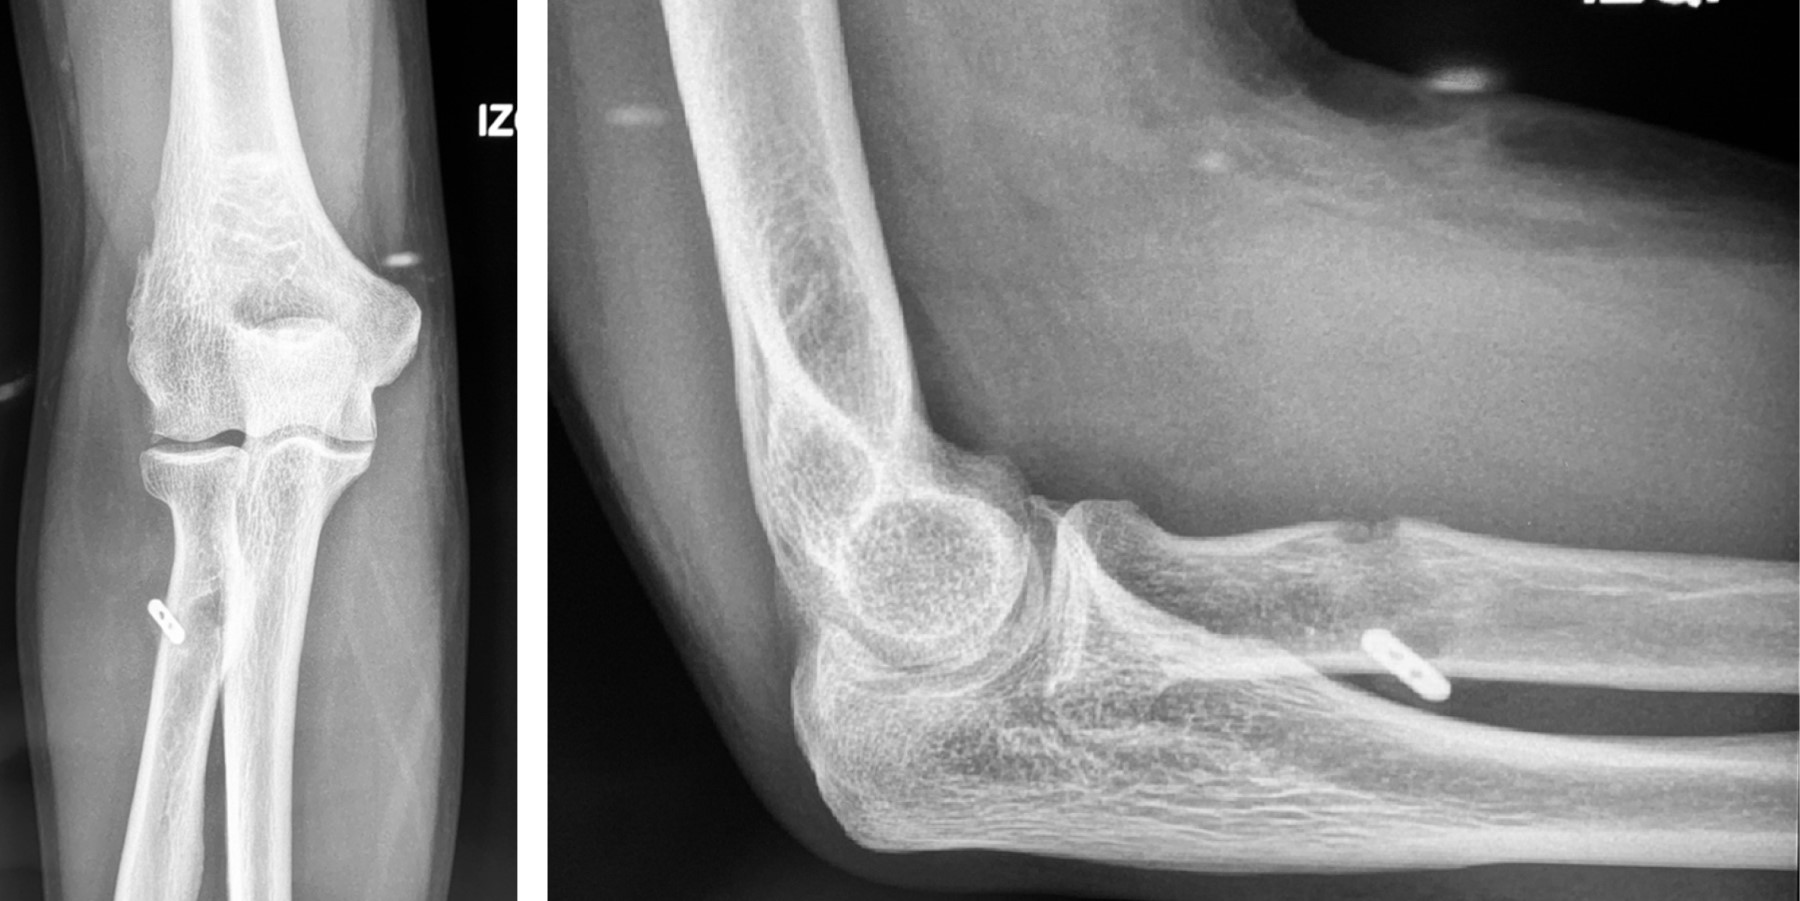

Distal biceps brachii rupture in a patient with COVID-19

Cuéllar-Avaroma A, King-Martínez M, Martínez-Oliva D, Rodríguez-Zulueta P, King-Martínez A

Introduction: distal biceps tendon injury commonly occurs in male patients between the fifth and sixth decade of life. The mechanism of the injury is an eccentric contraction with the elbow in flexion of 90 degrees. For its surgical treatment, several options have been described in the literature with different approaches, type of suture to be used and various methods of fixing the repair of the distal biceps tendon. The musculoskeletal clinical manifestations of COVID-19 are fatigue, myalgia, arthralgia, but the musculoskeletal effects of COVID-19 remain unclear. Case report: 46-year-old COVID-19 positive male patient with acute distal biceps tendon injury and secondary to minimal trauma, with no other risk factors. The patient was treated surgically following orthopedic and safety guidelines for the patient and medical staff due to the COVID-19 pandemic. The surgical procedure of the double tension slide (DTS) technique with a single incision in a reliable option and our case of a low morbidity, few complications and a good cosmetic option. Conclusion: the management of orthopedic pathologies in COVID-19 positive patients is increasing as well as the ethical and orthopedic implications of the management of these injuries and/or the delay of their care during the pandemic.

Figure 2